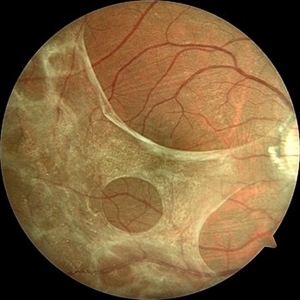

Color fundus photograph of the right eye of a 36-year-old man showing thickening of the posterior hyaloid associated with an epiretinal membrane due to ocular toxoplasmosis.

Photographer: Anyssa Montenegro, Centro Brasileiro da Visão, Brasília-DF, Brazil

Condition/keywords: epiretinal membrane (ERM), fundus photograph, ocular toxoplasmosis, thickening of the posterior hyaloid